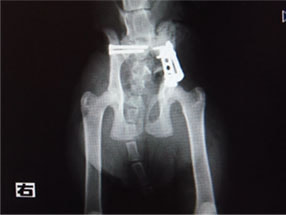

骨盤骨折 : 症例1 | 症例2 | 症例3 | 症例4

症例:交通事故による椎体脱臼

柴犬:9歳、避妊雌

交通事故直後、胸腰部に激しい疼痛、両後肢に完全麻痺を認め、シェフシェリントン徴候を呈していました。レントゲン検査において、第11-12胸椎間の脱臼が認められました。

脊髄の減圧、脊柱管の再構築・安定化を目的に、片側椎弓切除術およびMatrixMANDIBLE Plateによる椎体固定を実施しました。

隣接椎体を架橋するようにプレートを設置しました。

術後レントゲン写真